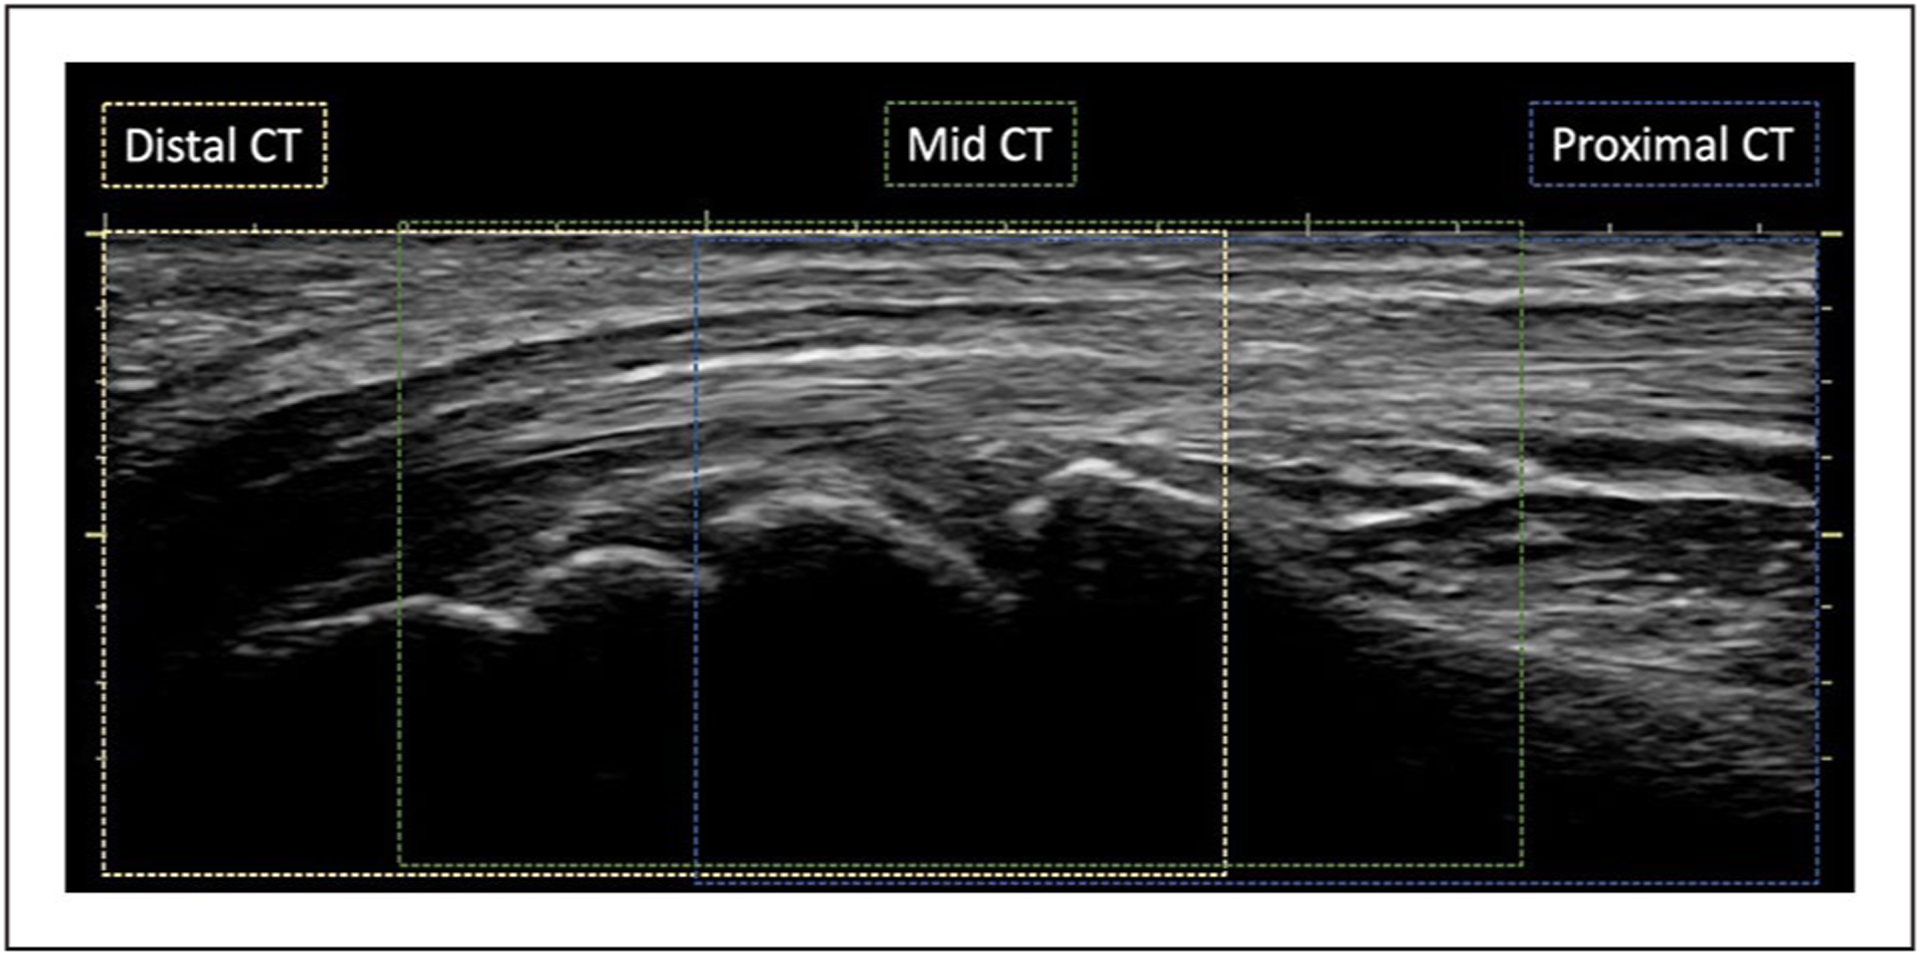

This study examined the implementation of a Doppler sonography imaging protocol to assess intraneural blood flow, within the median nerve, in healthy individuals.

A total of 176 participants were examined, and this involved 717 retrospective observations of the images collected. The implemented imaging protocol was assessed, and the data that were collected were cleaned and checked for fidelity and validity.

A large percentage of missing evidence (11%–35%) across proximal, mid, and distal carpal tunnel locations. Only a quarter of cases with evidence of intraneural blood flow had the strongest evidence of a power Doppler video clip, of which only three-quarters were valid. The study identified potential areas for improving the imaging protocol to reduce missing data and improve data quality.

This study demonstrates the significance of a standardized imaging protocol to guide the sonographic acquisition of Doppler images and provides important insights into potential issues with data quality. The recommendations have the potential to help future studies assess intraneural blood flow in healthy populations in a more rigorous and reliable way. Incorporating the study’s recommendations into a standardized protocol, there is potential to enhance the diagnostic accuracy of carpal tunnel syndrome and improve diagnosis and treatment.